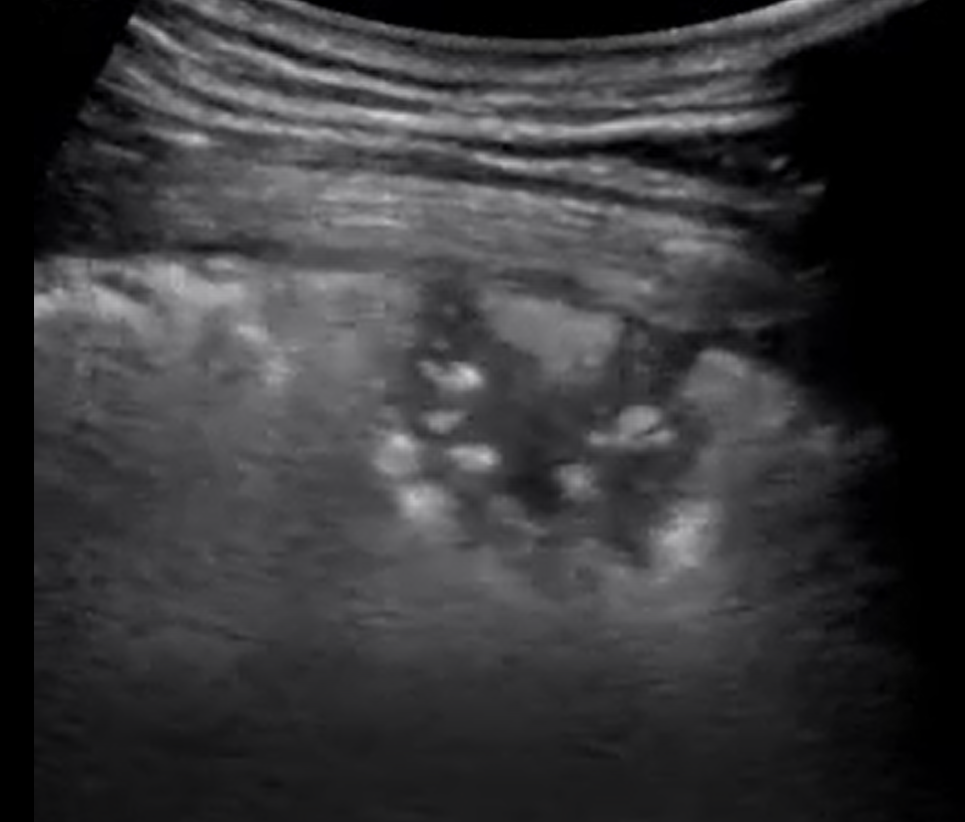

Ultrason cihazlarından alınan videolar kullanılarak derin öğrenme ve video işleme tabanlı bir model oluşturulmuştur. Geliştirilen model COVID-19 hastalarından alınan Akciğer Ultrason (LUS) kayıtlarını; sağlıklı kontrol, bakteriyel pnömoni ve viral pnömoniden başarılı bir şekilde ayırt edebilmektedir. Tasarlanan bu eğitilmiş model sayesinde COVID-19 sınıflandırılması geliştirilen web tabanlı yazılım prototiplemesi ile yapılabilmektedir.